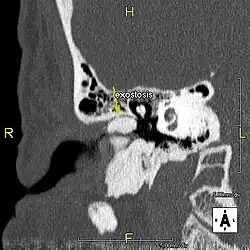

Description de cette image, également commentée ci-après

L'exostose du surfeur ou oreille de surfeur est une exostose, c'est-à-dire une croissance osseuse anormale, qui pousse vers l'intérieur du conduit auditif[1]. L'os entourant le conduit auditif réagit à l'agression thermique et mécanique de l'eau froide et de ses turbulences, par une nouvelle croissance osseuse qui a pour effet de resserrer le conduit auditif.

Du fait de la réduction du diamètre du conduit auditif, l'eau et le cérumen peuvent rester piégés entre la masse osseuse et le tympan et provoquer ainsi une infection comme une otite externe, particulièrement douloureuse.